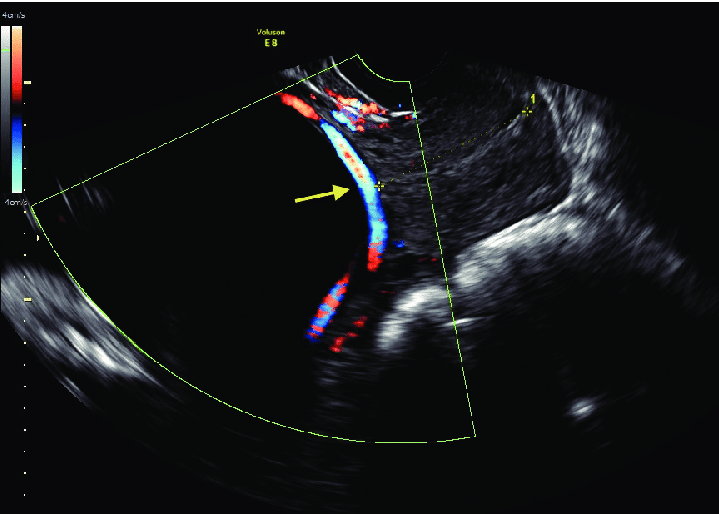

Portanto, todos os sangramentos da segunda metade da gravidez devem fazer suspeitar da possibilidade de uma implantação anômala do cordão. O melhor método para diagnosticar a vasa prévia é o ultrassom transvaginal. No ultrassom transvaignal com Doppler é possível ver os vasos correndo sobre o orifício do colo uterino.

Imagem de ultrassom de vasa prévia. O vaso do cordão passa sobre o orifício interno do colo uterino.